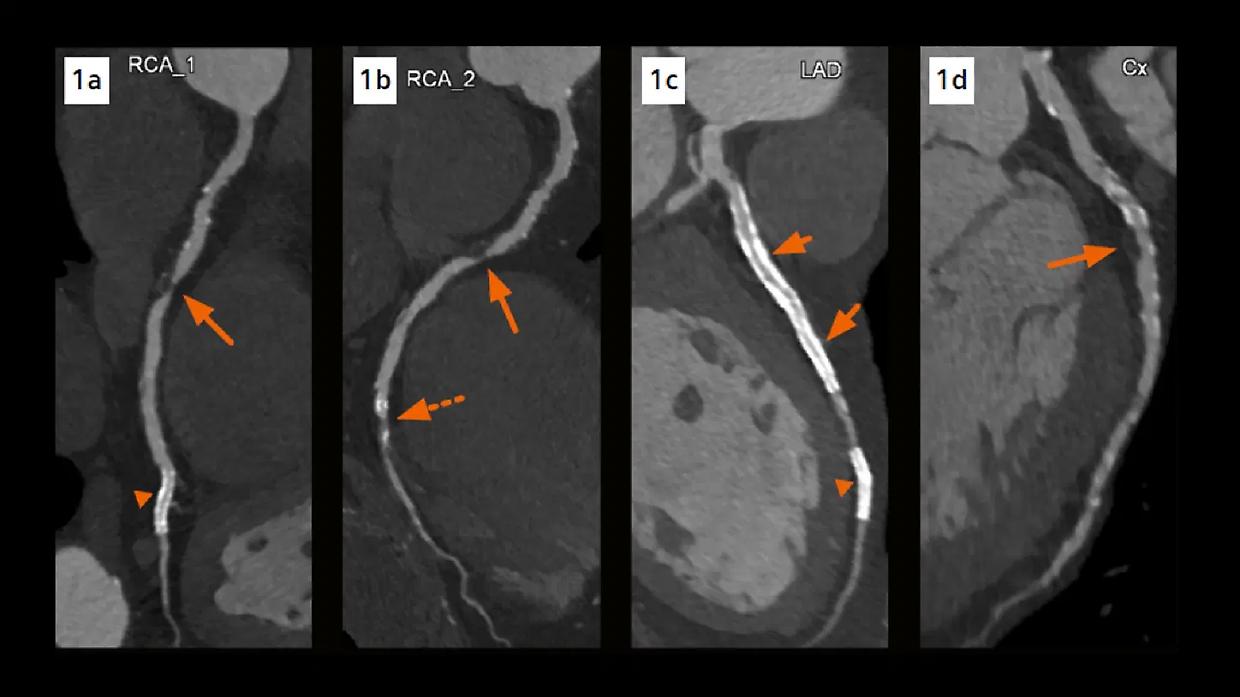

Al Congresso Europeo di Cardiologia di Madrid è stato presentato lo studio Pulse, un’analisi multicentrica che ha valutato l’efficacia della Tac coronarica di controllo nei pazienti sottoposti a stent nel tronco comune coronarico. I risultati, pubblicati sul Journal of the American College of Cardiology (JACC), mostrano che la Tac di follow-up non modifica i tassi di mortalità, ma riduce in modo significativo il rischio di infarto miocardico nei 18 mesi successivi rispetto al solo monitoraggio clinico dei sintomi.

Lo studio ha coinvolto 600 pazienti trattati con angioplastica e stent nel tronco comune, una delle aree coronariche più critiche. I partecipanti sono stati suddivisi in due gruppi: uno seguito con il tradizionale controllo clinico basato sui sintomi, l’altro con Tac coronarica di routine. Dal confronto è emerso che, pur senza incidere sulla sopravvivenza, la Tac riduce gli eventi ischemici maggiori nel breve-medio periodo.